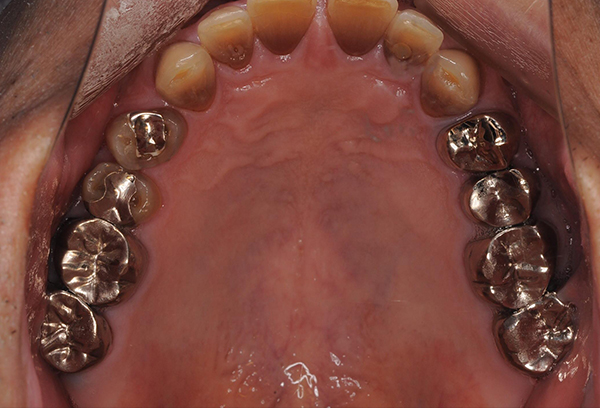

まず、歯の根の状態を確認するため、レントゲンで内部を確認します。抜歯しなくとも治せる可能性を診査・診断します。

マイクロスコープで根管内を拡大し、感染部位を映し出します。清掃にはリーマー、ファイルという専用の器具を使い、感染部位の取り残しがないように根の先まで隅々まで清掃します。